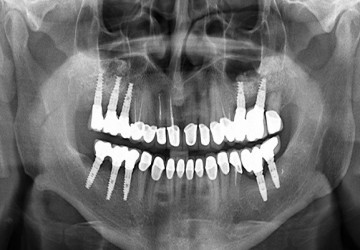

ایمپلنت از سه قسمت تشکیل شده 1.مهمترین جز آن پایه فلزی ایمپلنت دندان از جنس تیتانیوم و...

برخی از افراد به هر دلیلی ممکن است دندان های خود را از دست بدهند. همان طور که در عکس بالا...

ایمپلنت فوری یک روش نسبتا جدید برای جاگزینی دندان از دست رفته است. زمانی که به هر دلیلی شخ...